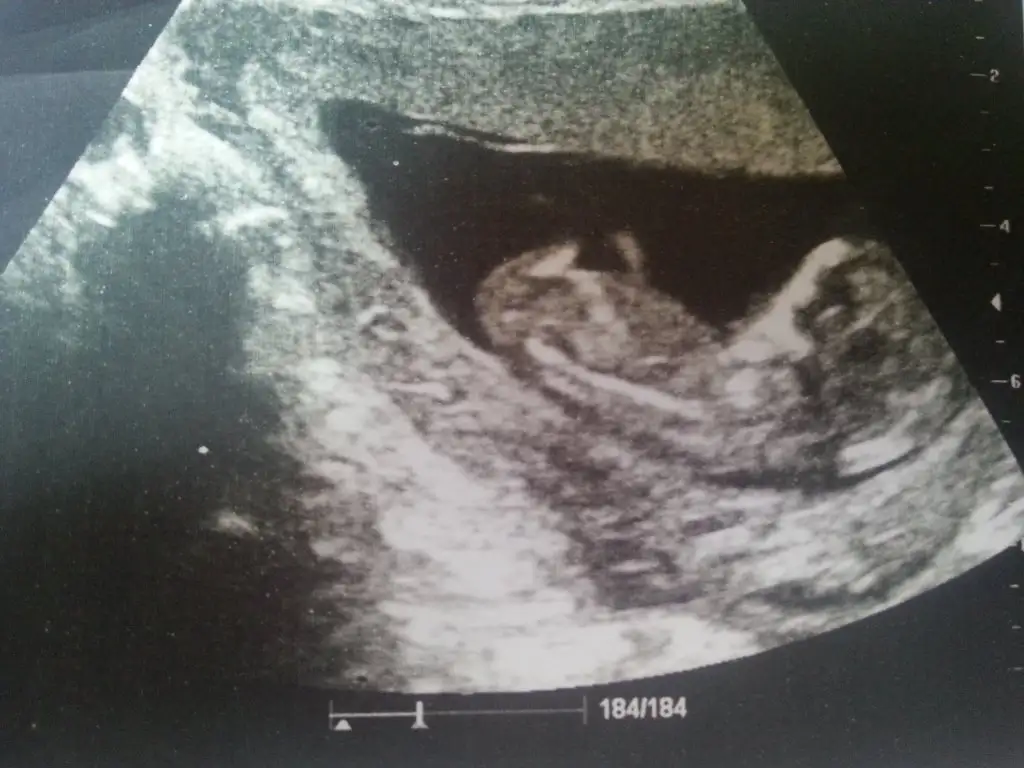

Çizgisi parelel ama bence bu bebis erkek

Çıkıntı yok nun çizgisi parelel kordonu parelel bu teoriye göre kız olmasi lazım ama benim içimden erkek gecti hayırlısi öğrenince yaz merak ettimAgzina saglik canim cok tesekkur ederim yarin kendi doktoruma gidicm insallah tahminini soyler birde su fotomuz var :)

Yazarim canim ben de % 99 erkek hissediyorumÇıkıntı yok nun çizgisi parelel kordonu parelel bu teoriye göre kız olmasi lazım ama benim içimden erkek gecti hayırlısi öğrenince yaz merak ettim

Erkekmiş bebeğimay bu da kızzz, bugün hiç erkek göremedim sanki daha